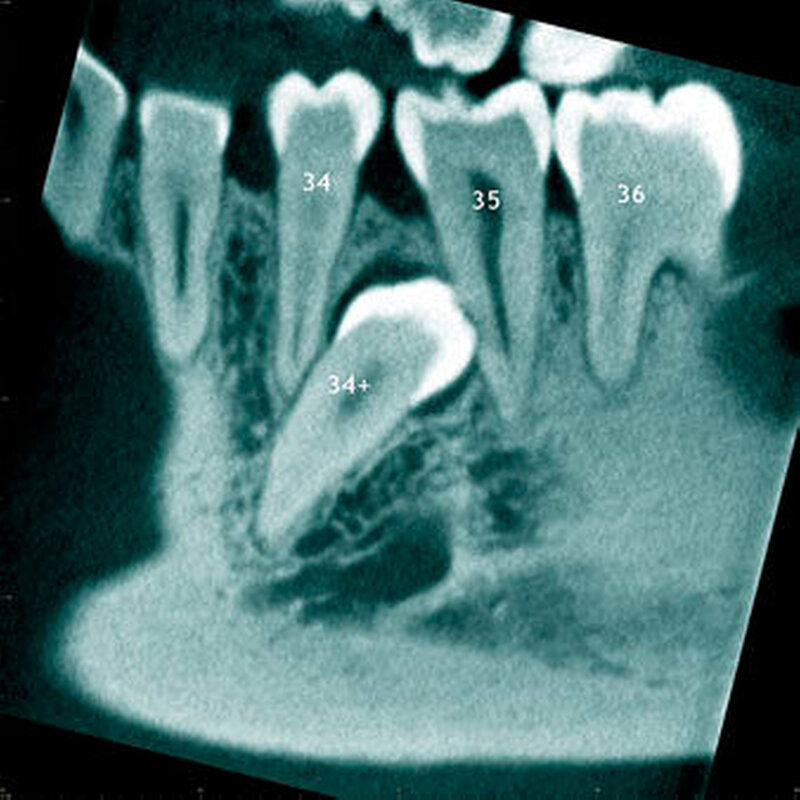

In einer aktuellen Arbeit berichteten Mossaz und Mitarbeiter (2014) über eine relativ hohe Prävalenz (22,8 Prozent) der Wurzel- resorptionen an benachbarten Zähnen, wobei besonders häufig überzählige Prämolaren zu Resorptionen führen (Abbildung 18). Für die Beurteilung der Wurzelresorptionen wurden digitale Volumentomografie (DVT) der Patienten herangezogen. In einer Studie aus China, welche ebenfalls DVT-Bilder beurteilte, wurde über eine deutlich geringere Häufigkeit von Wurzelresorptionen (1,6 Prozent) berichtet [Liu et al., 2007]. Im Gegensatz zu den Daten aus der Schweiz war Diagnose und Bewertung von Wurzelresorptionen kein primäres Ziel dieser Studie und es wurde auch keine Information über das Ausmaß der Resorptionen gegeben.

Daher könnte diese Studie leichte oder mäßige Wurzelresorptionen nicht eingeschlossen haben, was zumindest einen Teil des doch deutlichen Unterschieds in den Prozentsätzen erklären würde. Studien, welche Panoramaschichtaufnahmen zur Diagnose von Wurzelresorptionen heranziehen, berichten über Resorptionsraten zwischen 4,7 Prozent [Gündüz et al., 2008] und 7,6 Prozent [Hyun et al., 2009]. Tyrologou und Mitarbeiter (2005) berichteten sogar, dass keine Resorption im untersuchten Patientengut vorhanden waren. Allerdings wurden in dieser Studien nur Mesiodentes beurteilt, wo Wurzelresorption benachbarter Zähne eher selten vorkommen [Mossaz et al., 2014]. Generell lässt sich festhalten, dass zweidimensionale Röntgenaufnahmen für die Diagnose von Wurzelresorptionen eher ungenau sind und diese so in bis zu 50 Prozent der Fälle übersehen werden [Ericson Kurol, 1987, Heimisdottir et al., 2005; Botticelli et al., 2011; Alqerban et al., 2011a].